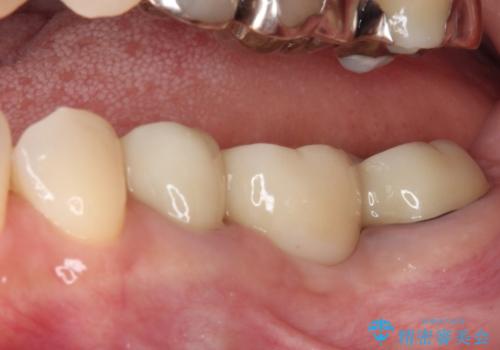

前歯は神経を取り除いて変色した歯や金属の縁が見える歯などがあり審美的に気になっていましたが、治療するかどうかは悩んでいらっしゃいました。

ところが、奥歯の治療を開始する前に、神経が失活して根尖部に病変のある前歯が著しく痛み出したため、根管治療を行うこととなりました。

奥歯の治療をしている間に前歯の治療をどのように勧めるのか検討していただき、最終的には4歯を一度に治療し、審美的に仕上げることとしました。